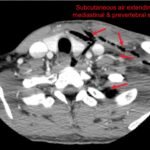

Necrotizing soft tissue infections with mediastinal extension are exceedingly rare. This submission provides dynamic and static visual stimuli (CT images) and a case report describing the history of present illness, initial ED presentation and inpatient course of a 33-year-old man who developed facial necrotizing fasciitis complicated by mediastinitis secondary to odontogenic infection following wisdom tooth extraction. Discussion of the key features of this rare presentation, the diagnostic and therapeutic approaches to making the diagnosis (including CT), and the role of the Emergency Physician, are highlighted.